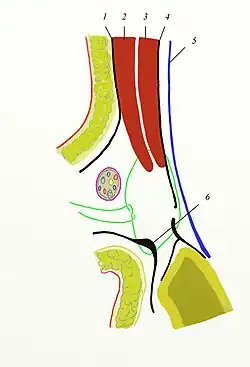

Inguinal hernia surgery is an operation to repair a weakness in the abdominal wall that abnormally allows abdominal contents to slip into a narrow tube called the inguinal canal in the groin region.

There are two different clusters of hernia: groin and ventral (abdominal) wall. Groin hernia includes femoral, obturator, and inguinal.[1] Inguinal hernia is the most common type of hernia and consist of about 75% of all hernia surgery cases in the US. Inguinal hernia, which results from lower abdominal wall weakness or defect,[2] is more common among men with about 90% of total cases.[3][4] In the inguinal hernia, fatty tissue or a part of the small intestine gets inserted into the inguinal canal.[5] Other structures that are uncommon but may get stuck in inguinal hernia can be the appendix, caecum, and transverse colon.[6] Hernias can be asymptomatic, incarcerated, or strangled.[3] Incarcerated hernia leads to impairment of intestinal flow, and strangled hernia obstructs blood flow in addition to intestinal flow.[1]

Inguinal hernia can make a small lump in the groin region which can be detected during a physical exam and verified by imaging techniques such as computed tomography (CT). This lump can disappear by lying down and reappear through physical activities, laughing, crying, or forceful bowel movement. Other symptoms can include pain around the groin, an increase in the size of the bulge over time, pain while lifting, and a dull aching sensation.[5] In occult (hidden) hernia, the bulge cannot be detected by physical examination and magnetic resonance imaging (MRI) can be more helpful in this situation.[7] Males who have asymptomatic inguinal hernia and pregnant women with uncomplicated inguinal hernia can be observed, but the definitive treatment is mostly surgery.[8]